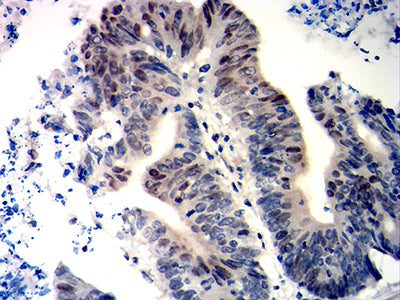

Immunohistochemical analysis of paraffin-embedded human colon cancer tissues using WT1 mouse mAb with DAB staining.